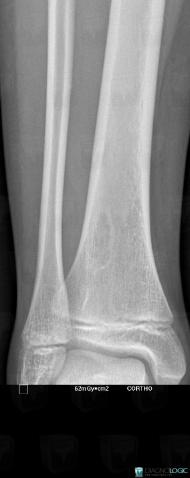

Fibrous cortical defect, Tibia - Distal part, X rays

Here is the specific information in the key image above:

- Diagnosis Fibrous cortical defect, Location(s) Tibia - Distal part, with gamuts Well-defined osteolysis